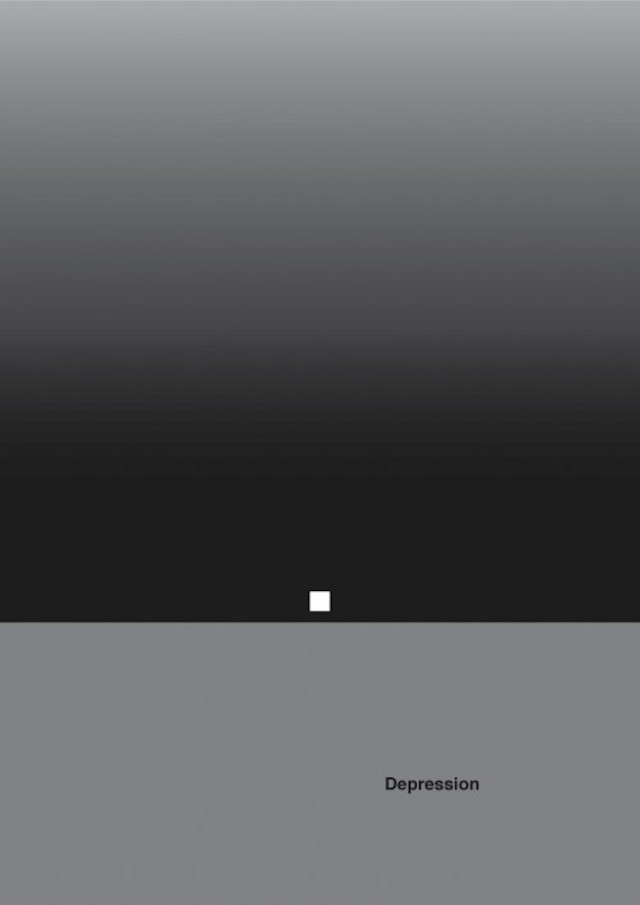

Like Christian Stoll who has put colors on psychology and emotions, Designer Patrick Smith managed to put graphic symbols on complex mental disorders. Through 7 minimalist posters and respecting precise color codes, we can decrypt the feelings of lack of understanding, division and isolation in certain psychological diseases.